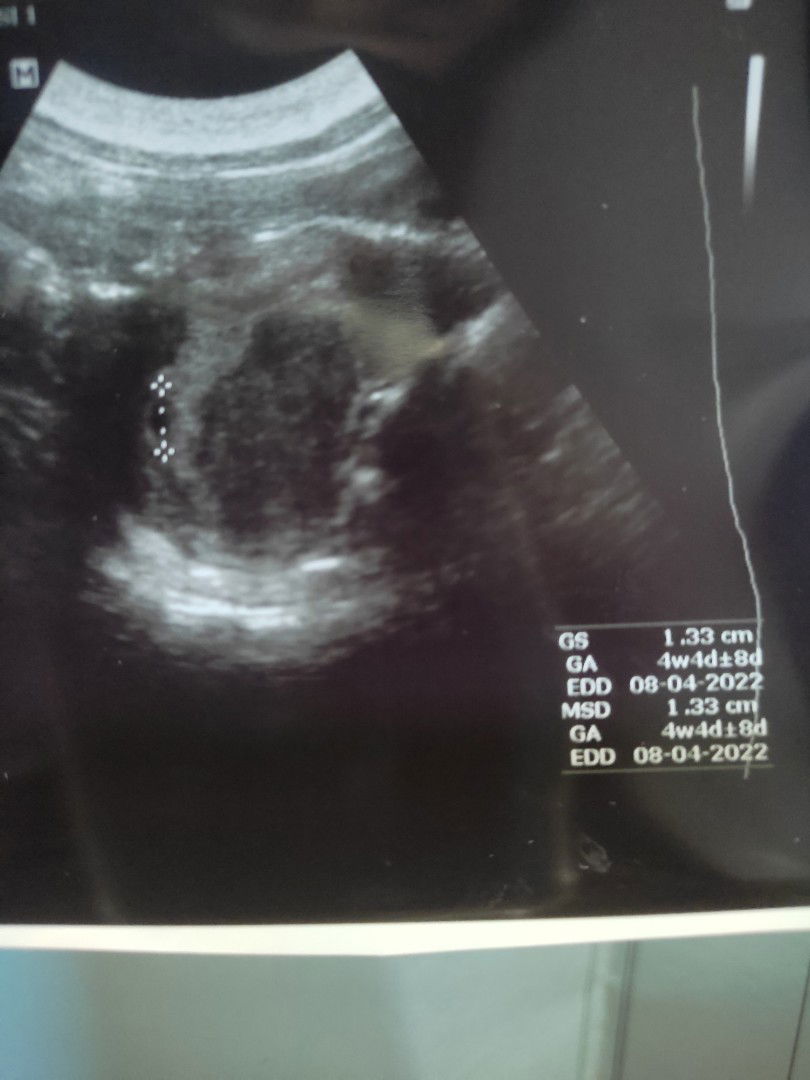

ini hasil USG hamil anak pertama bund. usia 5w3d pas ngeliat si adek reflek nangis bahagia. oiya saya hamil gak ada selera makan. tapi kalo makan mau aja tapi nanti muntah . tips nya bunda makanan apa yang bisa di konsumsi selain nasi dan buah. makasih